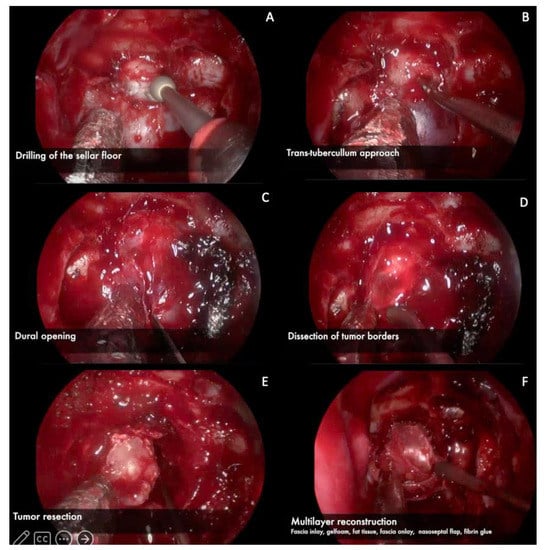

3.1. Endoscopic Endonasal Approach

3.1.1. Nasal Phase

3.1.2. Sphenoidal Phase

3.1.3. Sellar Phase

3.1.4. Closure